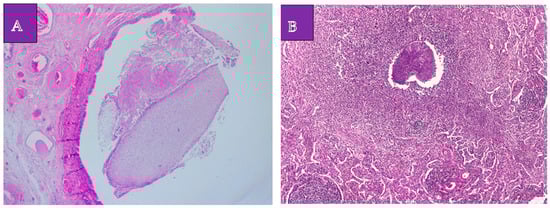

The histopathological examination established the diagnosis of a lung adenocarcinoma with a non-mucinous lepidic pattern situated in the upper apical segment, low-grade neuroendocrine tumor G1 (a typical carcinoid tumor) at the basal pyramid level (Figure 3A,B), and pulmonary aspergilloma (Figure 4A,B). In the case of the adenocarcinoma, the histological characteristics suggested an in situ/non-invasive lesion. Additionally, immunohistochemistry was performed, with tumor cell positivity for synaptophysin, chromogranin A, TTF1, and Ki67 at a rate of less than 2% (Figure 5A–C). The histopathological examination determined the pT1N0G1 stage of the carcinoid tumor.

Figure 3. Carcinoid tumor proliferation. (A). Hematoxylin eosin, 50×. Bronchial tissue, tumor parenchyma, and carcinoid tumor proliferation. (B). Hematoxylin eosin 200×. Carcinoid tumor proliferation: neuroendocrine monoform cells of variable size, arranged in solid cellular aggregates.

Figure 4. Lung aspergilloma. (A). Hematoxylin eosin 50×. Mycotic aggregate (aspergilloma) intrabronchial. (B). Hematoxylin eosin 100×. Mycotic aggregation (aspergilloma) in the lung parenchyma associated with acute inflammation.